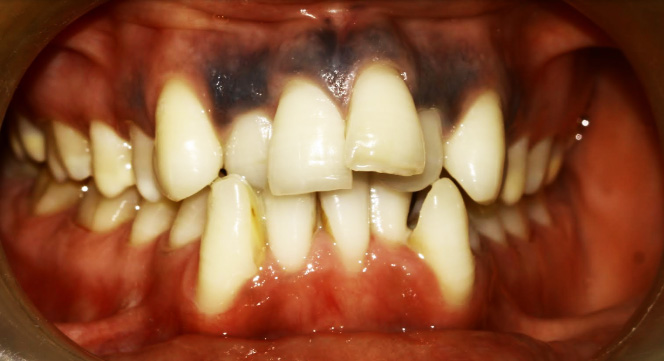

After Treatment (The Result)

After completion of orthodontic treatment, the patient showed:

• Properly aligned teeth

• Improved mouth closure

• A natural smile arc with improved esthetics, appearing even better than veneers

After-treatment images